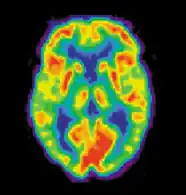

Позитронно-эмиссионная томография

Позитронно-эмиссионная томография (ПЭТ) измеряет выброс радиоактивно меченых метаболически активных химических веществ, введённых в кровеносное русло. Информация обрабатывается компьютером в 2- или 3-мерные изображения распределения этих химических веществ в головном мозге[7]. Испускающие позитроны радиоизотопы производит циклотрон и химические вещества маркируют радиоактивными атомами. Радиоактивно меченое образование, именуемое радиоактивный индикатор, вводят путём инъекции в кровеносное русло и в конечном счёте оно достигает головного мозга. Сенсоры в ПЭТ-сканере регистрируют радиоактивность, когда радиоактивный индикатор накапливается в разных структурах головного мозга. Компьютер использует информацию, собранную от сенсоров для создания 2- и 3-мерных разноцветных изображений, отражающих распределение индикатора в мозге. В настоящее врем нередко используются целые группы разнообразных лигандов для картирования различных аспектов активности нейромедиаторов. Тем не менее, наиболее часто используемым ПЭТ-индикатором остается меченая форма глюкозы (см. Фтордезоксиглюкоза (ФДГ)), показывающая распределение метаболической активности клеток головного мозга.

Самое большое преимущество ПЭТ в том, что разные радиоиндикаторы могут показывать кровообращение, оксигенацию и метаболизм глюкозы в тканях работающего мозга. Эти измерения отображают объём активности головного мозга в его разных участках и дают возможность больше изучить, как он работает. ПЭТ превосходит остальные методики, визуализирующие метаболизм в отношении разрешения и скорости (делает скан в течение 30 с). Улучшенная разрешающая способность дала возможность лучше изучить мозг, активированный определённым заданием. Главный недостаток ПЭТ заключается в том, что радиоактивность быстро распадается, это ограничивает мониторинг только коротких заданий[8]. До того, как стала доступной ФМРТ, ПЭТ была главным методом функциональной (в противоположность структурной) методикой нейровизуализации и до сих пор продолжает делать большой вклад в неврологию.

ПЭТ также используют для диагностики болезней головного мозга, в первую очередь потому что опухоли головного мозга, инсульты и повреждающие нейроны заболевания, вызывающие деменцию (такие как болезнь Альцгеймера) очень нарушают метаболизм мозга, что ведёт к легко заметным изменениям на ПЭТ-сканах. ПЭТ, вероятно, наиболее полезна в ранних случаях определённых деменций (классический пример — болезнь Альцгеймера и болезнь Пика), где ранние нарушения особо диффузные и ведут к слишком маленьким различиям в объёме мозга и его макроскопической структуре, чтобы быть заметными на КТ или стандартной МРТ, которые не имеют возможности отличить их от обычной возрастной инволюции (атрофии), не вызывающей клинической деменции.